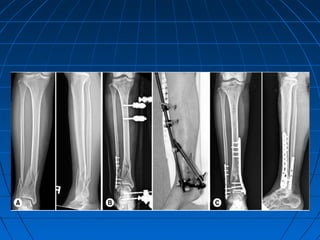

TIBIAL PILON FRACTURE RxTIBIAL PILON FRACTURE Rx

1.1. Plaster immobilizationPlaster immobilization

2.2. TractionTraction

3.3. Lag screw fixationLag screw fixation

4.4. OR & IF with platesOR & IF with plates

5.5. External fixation with orExternal fixation with or

without limited internalwithout limited internal

fixation.fixation.

Wait for 7 to 10 days for soft

tissue healing to occur before

planning surgery.